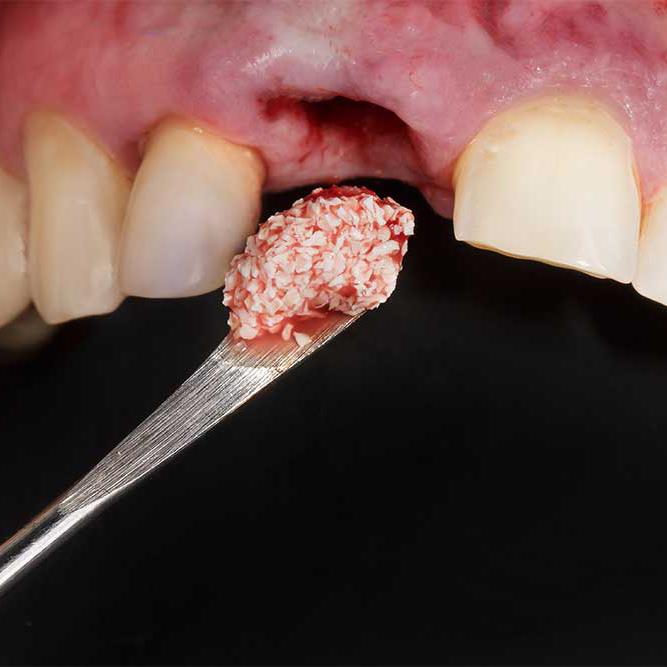

Kullandığımız tüm kemik grefti materyalleri UTTS onaylı, biyouyumlu ve uzun vadede güvenilirliği kanıtlanmış ürünlerden oluşmaktadır. Çeşitli biorejenerasyon yöntemleri ile kemik greftlerinin etkinliği ve başarısı artırılabiliyor.

Diş kemik grefti, çene kemiğinde erime ya da incelme olduğu durumlarda uygulanan bir işlemdir. Bu işlem sayesinde implant tedavisi ve estetik diş uygulamaları için uygun kemik hacmi oluşturulur. Diş kemik grefti ameliyatı, alanında deneyimli uzmanlarımız tarafından steril ve güvenli bir ortamda gerçekleştirilir.

Kliniğimizde ihtiyaç ve hasta durumuna göre farklı kemik grefti çeşitleri uygulanmaktadır:

Otojen greft (kişinin kendi kemiği)

Allogreft (donör kaynaklı)

Sentetik greftler

Hayvansal kaynaklı greftler

Hangi yöntemin uygun olduğuna detaylı muayene ve görüntüleme sonrası karar verilir.

Kemik grefti nasıl yapılır? sorusunun yanıtı kısaca şöyledir: Eksik kemik alanına uygun greft materyali yerleştirilir ve kemik ile bütünleşmesi için sabitlenir. Bu işlem lokal anestezi altında, konforlu şekilde gerçekleştirilir.